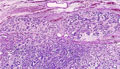

• 胸膜中皮腫ミクロ像(HE弱拡大)